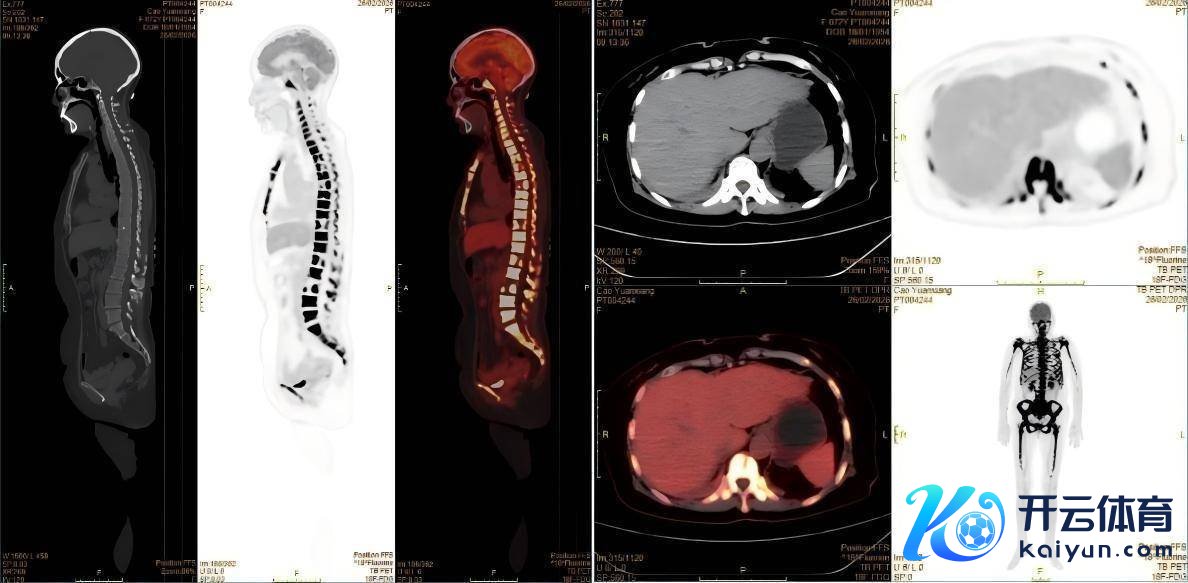

经PET-CT搜检,患者全身骨足够性赫然代谢增高,其他脏器均并未找到明确的实体原发灶,这么的显像效果推翻了肿瘤骨转化的初步会诊。核医学科医师看到这么的显像效果,并联结患者的临床发扬,一个新的会诊标的在脑海中触动:淋巴瘤?血液系统疾病?按照这一标的,为患者进一步进行了骨髓穿刺等搜检,终于这个凶犯被找到——急性淋巴细胞白血病。

△患者PET-CT的显像图

急性淋巴细胞白血病是一种发祥于淋巴细胞的恶性肿瘤,其荒谬增生的白血病细胞会浸润全身骨骼和骨髓,挫折骨代谢均衡,导致骨骼出现足够性代谢活跃和浓聚发扬。这恰是患者在PET-CT和骨扫描上出现荒谬浓聚的原因。同期,患者握续发烧、体重骤降等症状,亦然白血病细胞大王人增殖、开释致热原并禁止机体平日免疫功能的典型发扬。